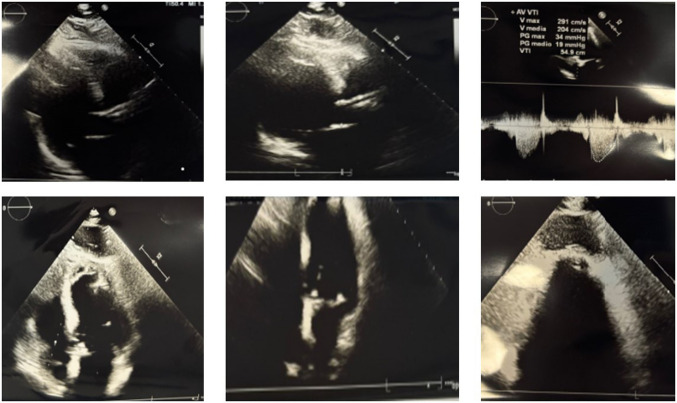

对症状性主动脉瓣狭窄的干预决策应权衡手术和经导管主动脉瓣植入术(TAVI)的风险。TAVI是一种成熟的技术,用于治疗老年和高危主动脉狭窄患者,采用多种不同的手术入路(逆行经股动脉、经腋窝、经主动脉或顺行经根尖入路)。经根尖入路需要心脏外科医生的参与,现在仅限于不能通过其他入路进行手术的病例。我们报告一例87岁的患者,患有严重外周动脉疾病,有经根尖入路TAVI病史,术后4年出现晕厥发作。影像学显示左心室顶动脉瘤,可能与先前的经根尖TAVI有关。该病例强调了在接受其他TAVI通路的患者中进行彻底的术前评估和长期随访的重要性,以及需要提高对罕见但重要的并发症(如心室假性动脉瘤)的认识。谨慎的患者选择和个性化的程序规划仍然是优化这一复杂人群结果的必要条件。

Decision-making for intervention in symptomatic aortic stenosis should balance the risks of surgery and of transcatheter aortic valve implantation (TAVI). TAVI is a well-established technique for treating elderly and high-risk patients with aortic stenosis using a variety of different surgical approaches (a retrograde transfemoral, transaxillary, transaortic or an antegrade transapical approach). The transapical approach requires the involvement of the heart surgeon and is now limited to cases where the procedure cannot be performed by alternative approaches. We report the case of an 87-year-old patient with severe peripheral arterial disease and a history of TAVI via transapical approach, who presented with a syncopal episode 4 years post-procedure. Imaging revealed a left ventricular apex aneurysm, likely related to the previous transapical TAVI. This case underscores the importance of thorough pre-procedural assessment and long-term follow-up in patients undergoing alternative TAVI access routes, as well as the need for heightened awareness of rare but significant complications such as ventricular pseudoaneurysm. Careful patient selection and individualized procedural planning remain essential to optimize outcomes in this complex population.